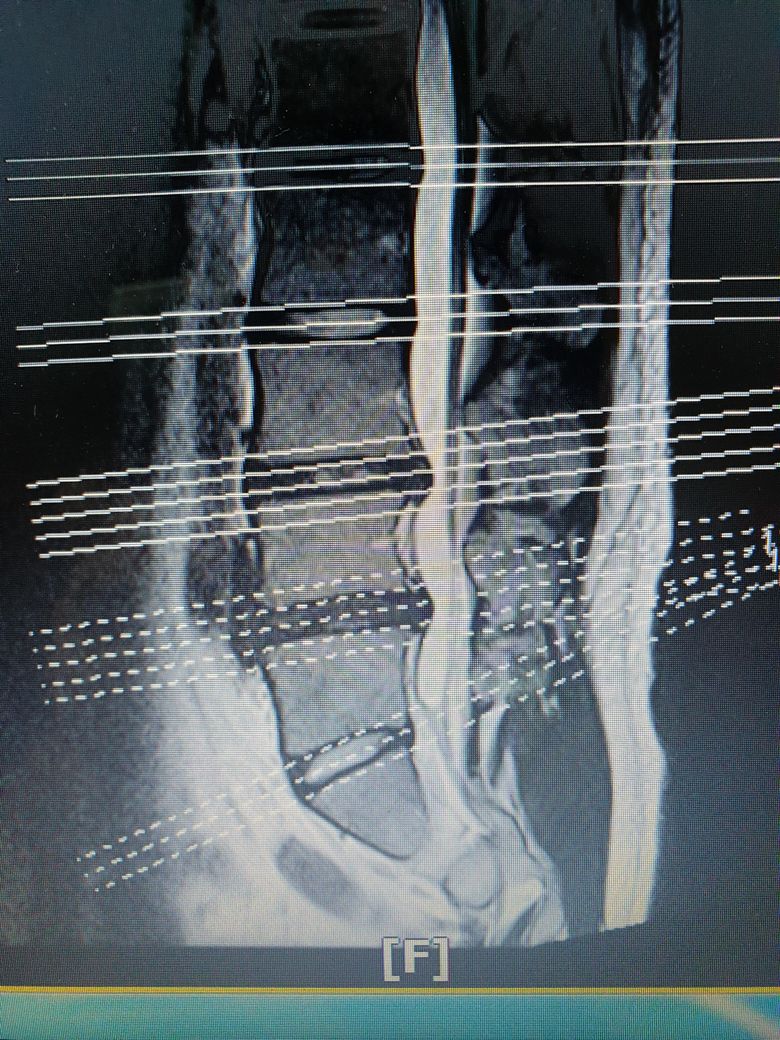

• 1번 째 사진

현재 mri에서는 3/4뿐만 아니라 4/5 디스크 역시 튀어나와있습니다. 물론 영상에서 보이는 소견도 중요하지만 증상도 중요합니다. 디스크는 가운데에 80%의 수분성분의 젤리처럼 생긴 수핵과 수핵을 보호하기 위해 섬유테들이 주위를 둥글게 감싸고 있습니다. 나이가 들어 수핵의 수분 함량 감소로 탄력성이 떨어지거나 외부적인 자극으로 디스크가 나오면서 신경을 눌러 통증을 일으킵니다. 젊은 연령층에서는 수핵의 탄력성이 유지되어있기 때문에 디스크가 나오더라도 다시 흡수되는 경우도 많이 있습니다. 일단 보존적 치료(물리치료, 재활운동, 보조기 착용, 주사 치료) 등으로 경과를 확인한 뒤 3개월 이상 보존적 치료에 효과가 없다면 수술적인 치료를 시행할수 있습니다.

4-5번은 이전에 어느정도였는지 알아야 얼마나 흡수됐는지 알 수 있습니다. 지금은 3-4번과 4-5번이 비슷한 정도로 튀어나와있습니다.

하지만 보여주신 sagittal view 만 봐서는 이렇게 튀어나간 디스크가 신경의 뿌리를 누르는지 아닌지 알아볼 수 없습니다. transverse view응 함께 봐야합니다.